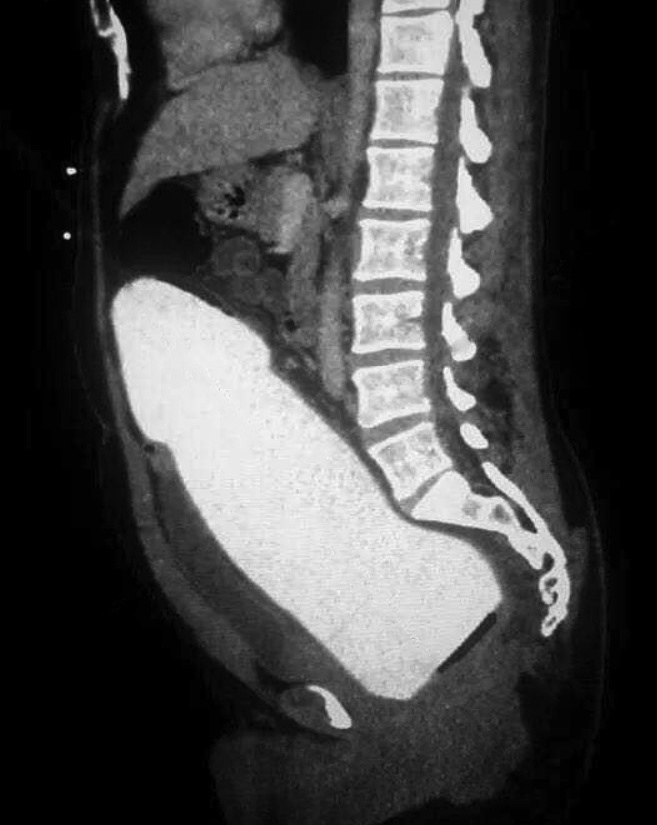

В одну из японских клиник поступил мужчина с необычной проблемой. В его прямой кишке застрял большой резиновый предмет.

Никто не предполагал, что ситуация закончится так удачно. Врачи и сам пациент были поражены, когда история пошла неожиданным образом. Ранее мужчина часто жаловался на резкие боли в пояснице. Оказалось, что использование этого предмета вызвало необычный эффект: он сместил крестец и устранил источник боли.

После извлечения предмета боли прошли, и пациент почувствовал значительное улучшение.